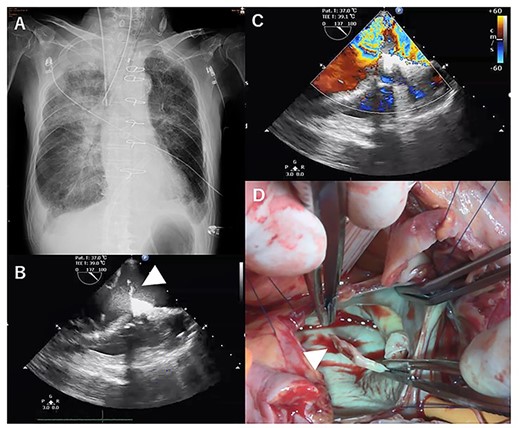

However, he again developed severe cardiogenic shock suddenly on POD 14 (Fig. 3A). Transthoracic echocardiography showed PMR and severe mitral regurgitation (Fig. 3B–D). VA-ECMO was restarted on the general ward, and the patient was transferred directly to the OR. Emergency mitral valve replacement with a biological prosthesis (Magna Ease 27 mm, Edwards Lifesciences, Irvine, CA, USA) was performed in the standard fashion. Intraoperatively, the ruptured posterior papillary muscle was confirmed. VA-ECMO could be weaned immediately after the surgery. After the two emergency operations, his course was uneventful, and he gradually recovered. He was then transferred to another hospital on POD 77 for rehabilitation.

X-ray at 14 days after first operation (A). transthoracic echocardiographic images showing posterior papillary muscle rupture (arrowhead, B) (C). Posterior papillary muscle rupture (arrowhead, D).